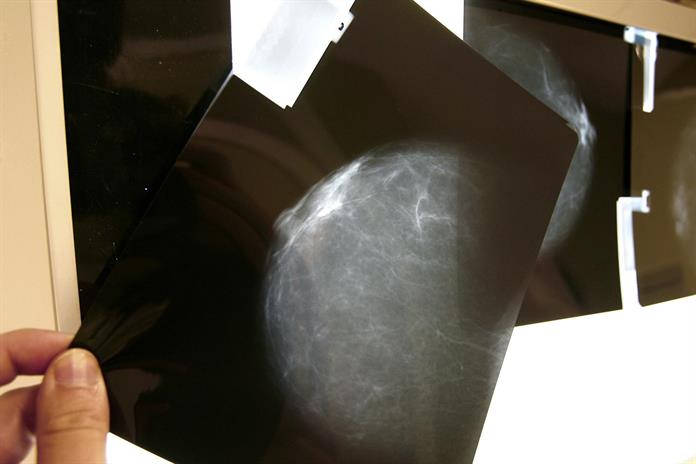

Un estudio del Instituto de Salud Carlos III de España, basado en el análisis de 714 pacientes con cáncer de mama, sugiere que tener mayor densidad mamográfica podría estar relacionado con el desarrollo de algunos tumores, como los HER2+ o los triple negativo, que son los más agresivos y con peor pronóstico.

La densidad mamográfica mide la proporción de tejido fibroglandular de una mama, frente a la cantidad de tejido graso. Cuanto más densas, más tejido fibroso tienen y mayor es el riesgo de cáncer de mama.

El 69% de las participantes presentó tumores HR+, un 19% el subtipo HER2+ y un 12% el triple negativo, y la densidad mamográfica media fue del 26%.

Las mujeres con densidad mamográfica superior al 50% presentaron un menor porcentaje de tumores con mejor pronóstico (HR+), mientras que el porcentaje de tumores HER2+ y triple negativo -los más agresivos- fue un 36% y un 23% mayor, respectivamente, en comparación con las mujeres del grupo de menor densidad.